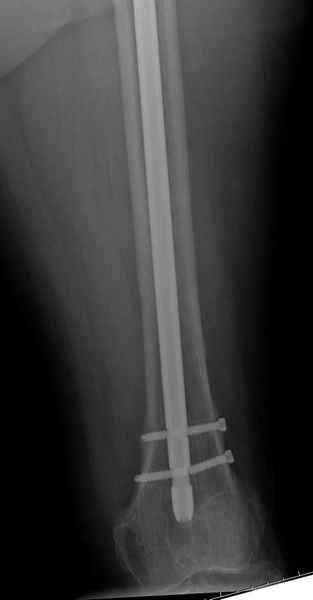

77 летняя больная направлена в нашу клинику на дальнейшее лечение. Из истории, травму получила в сентябре 2007 года и по поводу перелома шейки бедра больная была проперирована тремя каннюлированными шурупами с явным нарушением технологии установки шурупов. Внизу вместо одного шурупа имеется два, что привело к стрессу латерального кортекса. Через месяц по поводу ятрогенного подвертельного перелома сделана фиксация длинной Гамма 3. Установлен без проксимальной блокировки? (set screw). В данный момент имеется несостоятельность конструкции и ложный сустав. Передвигается с помошью костылей, конечность укорочена на 2 см. Какие будут рекомендации?Djoldas Kuldjanov, MDDepartment of Orthopedic SurgerySt. Louis University Medical Center

Михаил, здравствуйте. Если присмотреться - на четвертом снимке есть перелом гвоздя по отверстию.

Видимо, проблем тут две: во-1-х, центральный отломок был оставлен в варусно-сгибательной установке, во-2-х, не динамизировали вовремя.

Нижние винты хотели сломаться, но, увы, один не сломался, и тогда сломался гвоздь. Хотя и при динамизации в таком положении отломков

могло не срастись.